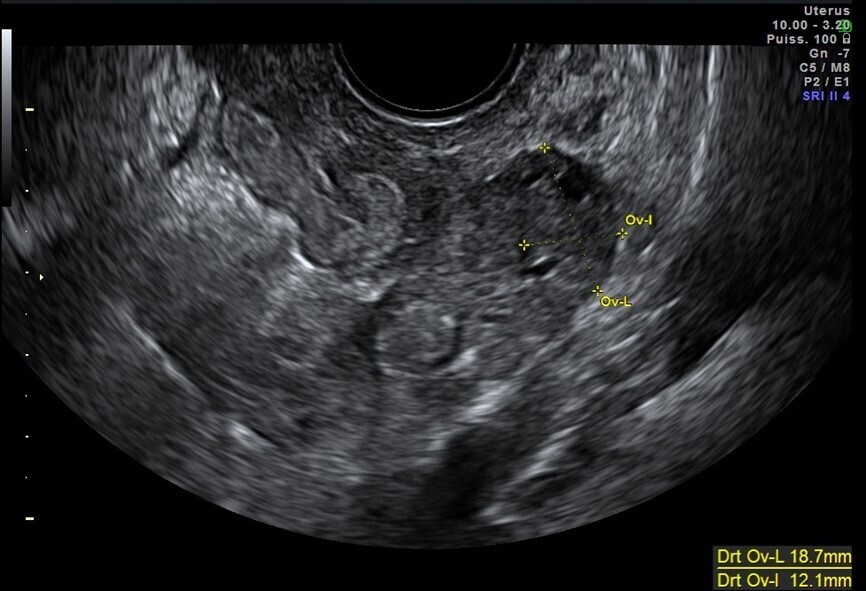

Vous faites une échographie pelvienne qui retrouve un utérus antéversé avec un endomètre épaissi de 5 mm, des ovaires droit et gauche sans anomalie. Il n’y a pas d’épanchement dans le cul-de-sac de Douglas.

La douleur n’est pas latéralisée et il n’existe pas de kyste ovarien.

On note l’absence de kyste sur les ovaires, même affaissé, associée à un cul-de-sac de Douglas sec.